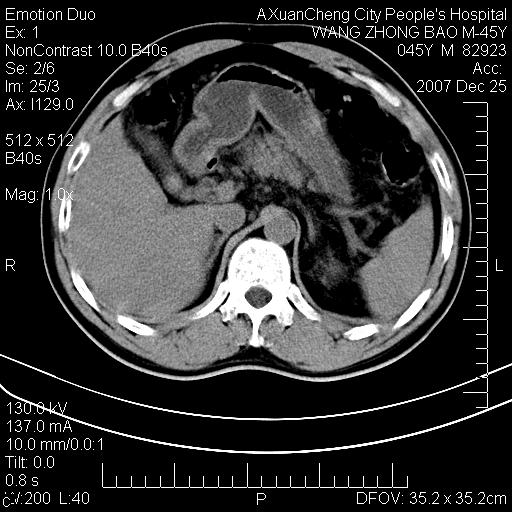

以下是引用qiuleiyu在2007-12-25 18:14:00的发言:[br]胰腺增大,周边渗出改变,肾前筋膜明显增厚,示少量积液.胆囊壁毛糙,周边少许渗出,胆总管壁厚,异常强化,然扩张不明显.结合病程急短;考虑;胆管炎,胆囊炎,胆源性胰腺炎可能大,请结合实验室检查及随访.

以下是引用lisihao在2007-12-25 14:23:00的发言:[br]急性水肿型胰腺炎[br]依据:1、胰腺弥漫性肿大,边缘稍毛糙;[br] 2、双侧肾周筋膜增厚,尤以左侧为甚(重要征象)[br] 3、双侧后胸膜增厚(刺激性炎症);[br] 4、结合病史,查血尿淀粉酶应该可以确诊。